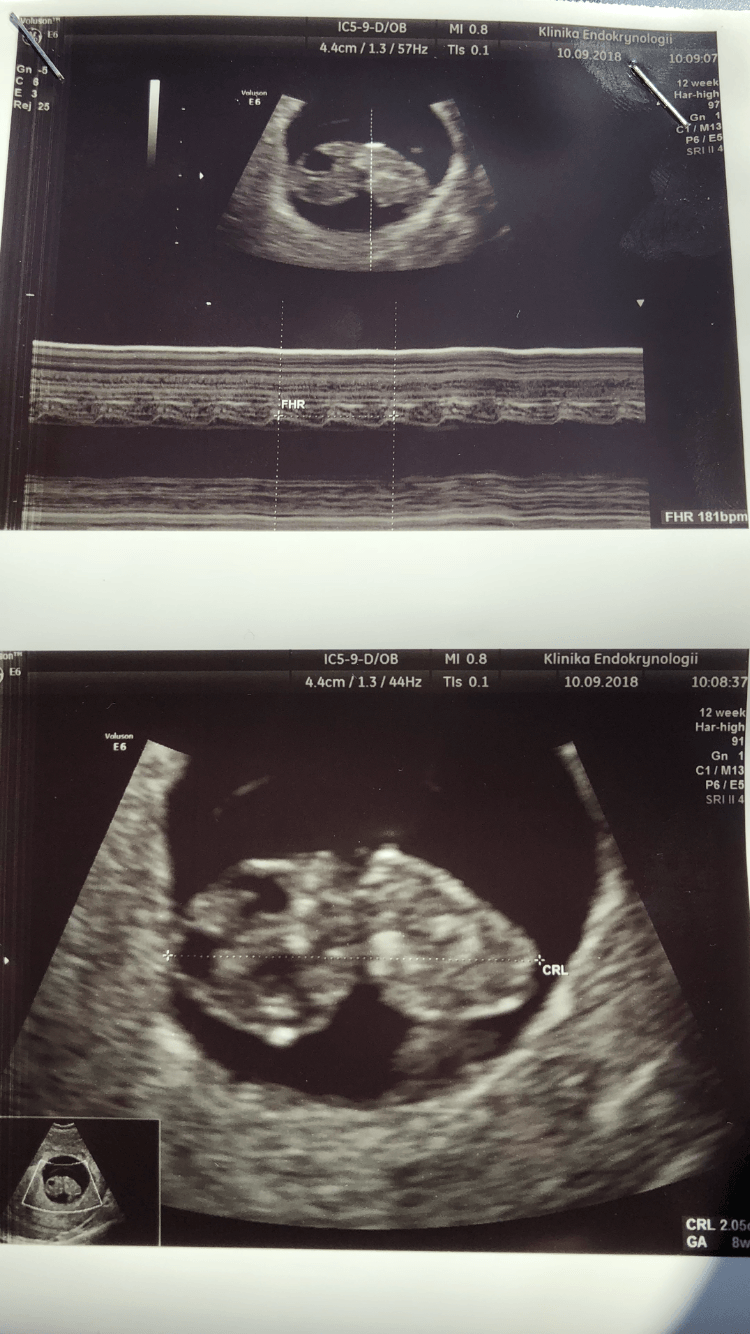

Czesc dziewczyny :) u nas wszystko dobrze! Bobas rosnie jak trzeba❤️ Ma „ już” 2 cm!!!!:)

Serducho bije jak szalone! Kolejne spotkanie za 2 tygodnie:)